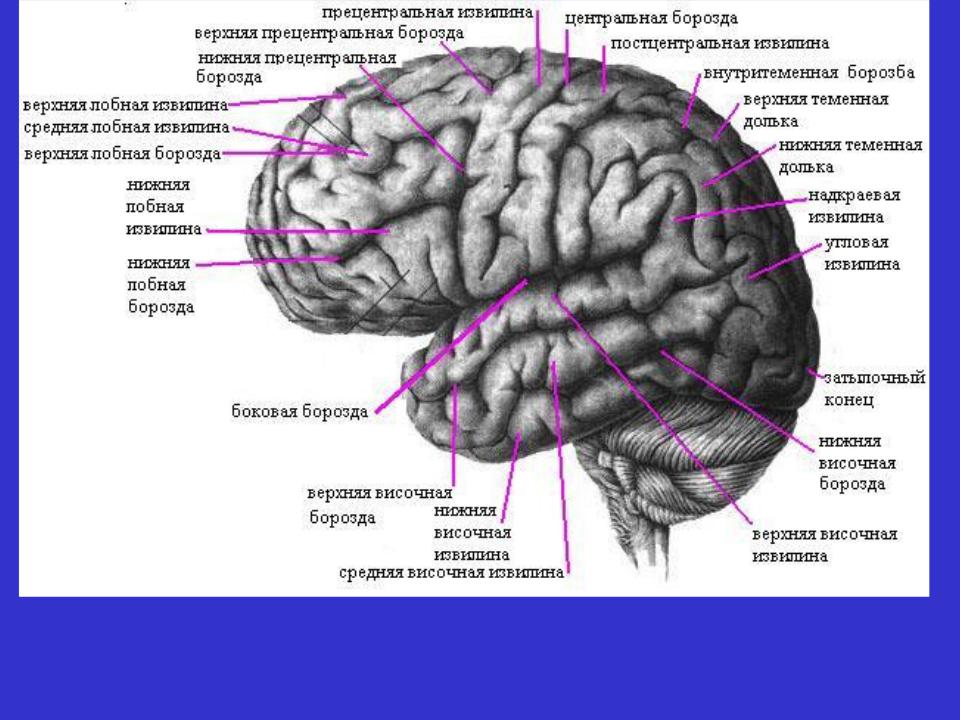

Схема чувствительных зон новой коры мозга